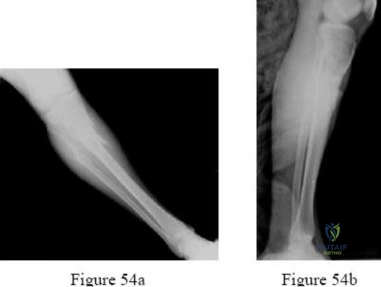

Question 6:

A 45-year-old male suffers a Gustilo-Anderson IIIB open tibia fracture with a 10 cm soft tissue defect over the distal third of the tibia, exposing the bone without periosteal coverage. After serial debridements and skeletal stabilization, what is the most appropriate soft tissue coverage option?

Correct Answer: Free tissue transfer (e.g., anterolateral thigh or latissimus dorsi flap)

Explanation:

Soft tissue defects over the distal third of the tibia that expose bone lacking periosteum require robust coverage. Rotational muscle flaps are geographically limited: the medial gastrocnemius covers the proximal third, and the soleus covers the middle third of the tibia. For the distal third, a free tissue transfer (such as an ALT, gracilis, or latissimus dorsi flap) is the gold standard for reliable coverage. A reverse sural flap is an option for smaller defects, but a 10 cm defect typically necessitates a free flap.

Question 27:

A 45-year-old male sustains a high-energy tibial pilon fracture. The initial presentation includes severe soft tissue swelling, massive fracture blisters, and skin tenting. What is the most widely accepted initial management strategy for this patient?

Correct Answer: Spanning external fixation across the ankle joint with delayed definitive fixation

Explanation:

High-energy pilon fractures with severely compromised soft tissues (swelling, blisters) are at extremely high risk for wound necrosis and deep infection. They are best managed with a staged protocol: initial spanning external fixation to restore length and alignment, followed by definitive ORIF once the soft tissues have recovered (typically 10-21 days later), evidenced by the return of skin wrinkles.